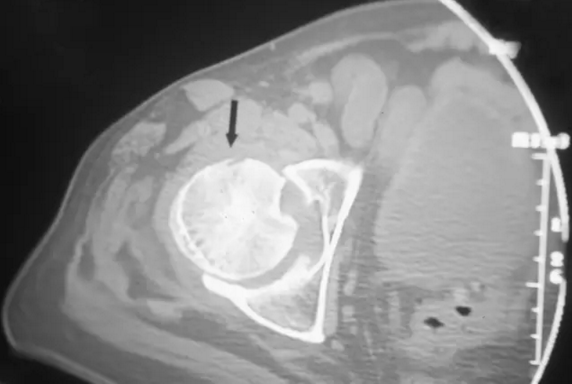

正常的轴向CT显示在股骨头内的突出和增厚但正常的小梁(箭头)。 注意从中心密集带以径向方式发出的细腻、硬化、射线状的分支形状。

CT检查诊断股骨头缺血坏死较X线片敏感,可早期发现微小的病灶、软骨下骨板微骨折等,对于股骨头缺血坏死的分期有着重要的意义,根据CT检查所见进行分期较X线片更准确。

对股骨头缺血坏死的患者CT显示中央小梁的聚集和变形。